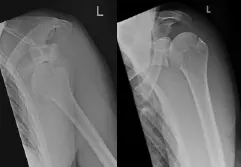

Abbildung: Typisches Röntgenbild einer ausgekugelten Schulter vor (links) und nach Reposition (rechts).